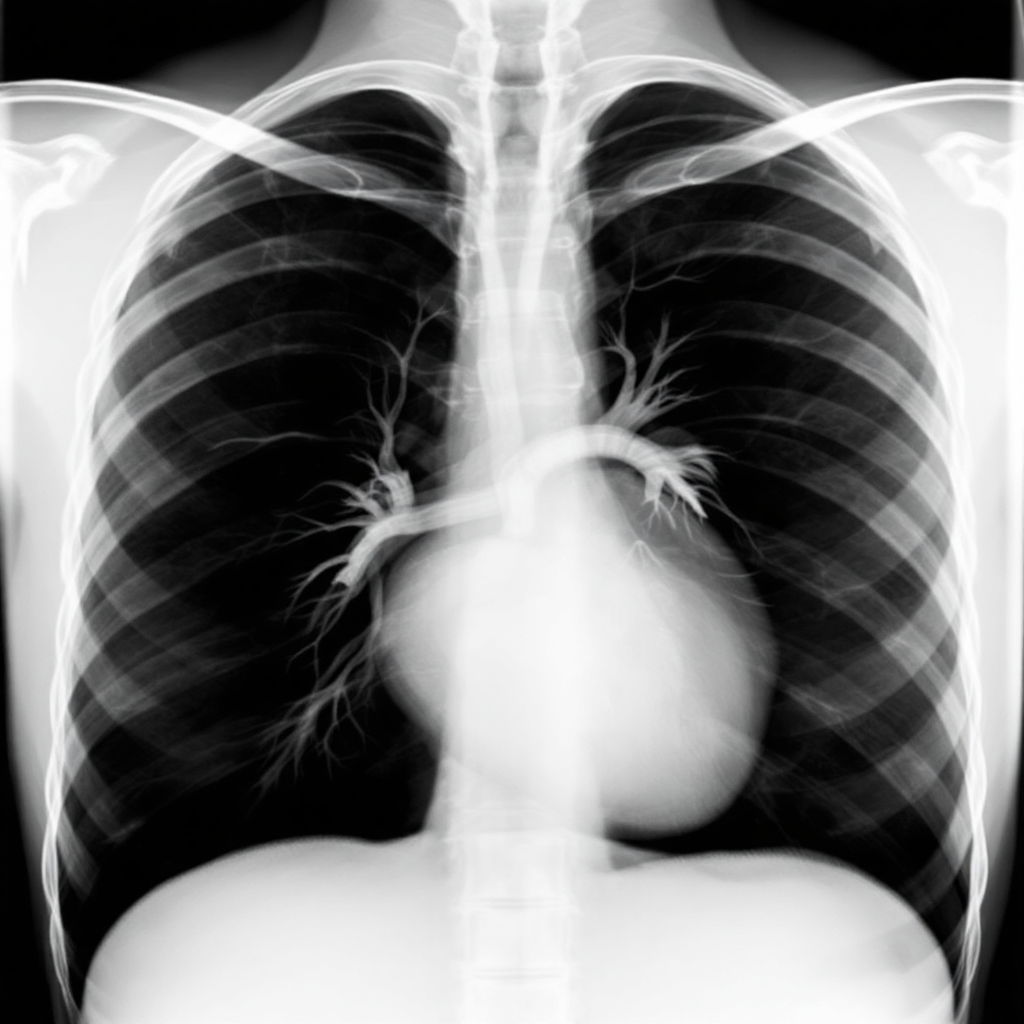

흉막삼출이 의심될 때 첫 단계는 흉부 X-ray 촬영이에요. 특히 측면 엎드린 상태에서 촬영하는 측와 촬영이 흉막강에 고인 액체를 가장 잘 보여줘요.

CT 스캔은 X-ray보다 더 정밀한 진단을 가능하게 해줘요. 액체의 양뿐 아니라 주변 조직 침범 여부나 종양 유무도 파악할 수 있어요. 암성 흉막삼출 의심 시 꼭 필요한 검사죠.

| X-ray | 비용 저렴, 초기 확인 가능 | 소량 흉수는 확인 어려움 |